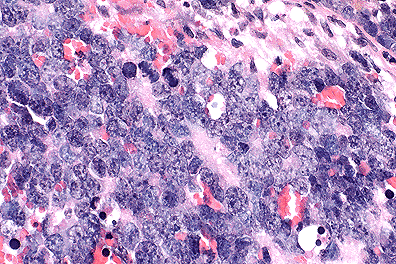

Retinoblastoma cells in a mouse. (40X, HE, 103K)

Morphologic Diagnosis: Eye: Retinoblastoma, FVB line 19, Mus musculus, rodent.

Contributor's Comments: The ocular mass, which in most sections is confined to the globe, is composed of pleomorphic, poorly differentiated, neoplastic retinoblasts arranged in cords and sheets. The cells are polygonal with scant cytoplasm and large "open-faced" basophilic nuclei with prominent nucleoli. There are numerous normal and bizarre mitotic figures and large foci of necrosis within the body of the mass.

Multinucleate cells are frequent and randomly distributed throughout the mass; some of these are degenerate. In some sections, extension of neoplastic cells into the optic nerve can be seen and in other sections, the degenerate lens is seen.

AFIP Diagnosis: Eye: Primitive neuroectodermal tumor, FVB line 19 transgenic mouse, rodent.

Conference Note: The retina is formed from neuroectodermal cells which line the floor of the primitive forebrain. Retinoblastomas arise from the neuroectoderm of the optic cup. In this case, the tumor appears to originate at the optic cup and expands into the vitreous chamber, elevating and detaching the retina. The tumor also invades the optic nerve in some sections, a common finding in retinoblastomas. This case was reviewed by the staff of the Department of Ophthalmic Pathology, AFIP. They believe that this tumor is neuroectodermal, but lacks sufficient differentiation to be definitively classified as a retinoblastoma. Thus, a diagnosis of primitive neuroectodermal tumor is favored.

The Rb gene is a tumor suppressor gene. Tumor suppressor gene protein down regulates cell proliferation. In humans, 60% of retinoblastomas occur sporadically, and the other 40% are familial. This ratio of occurrence has been explained by the "two hit" hypothesis. In familial cases of retinoblastoma, an individual is born with a mutant Rb gene on a single allele, the first hit. The second hit is a mutation of the second allele of a retinal cell that carries the original mutant allele. In sporadic cases, mutation of both alleles must occur in a single retinal cell. In either case, the retinal cell loses both copies of the Rb gene and unregulated proliferation ensues. As the contributor notes, FVB 16 mice carry the human papilloma virus 19 E6 and E7 genes. The gene products of E6 and E7 interact with the Rb gene product, interfering with the regulatory mechanism of the Rb gene product. Although the mechanism of inactivation is different between naturally occurring cases in humans and the transgenic mouse model, the end result is the same; loss of down regulation by Rb gene product and tumor formation.